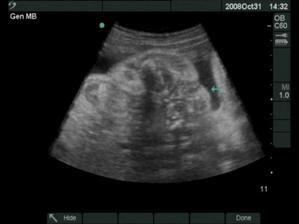

Moje tehotenstvo a naše bábätká

18.12.2008 prišli na svet o 3 týždne skôr naše krásne dvojičky. Ako prvá predrala cestu svojmu bratčekovi Laura, ktorá išla hlavičkou. Prišla na svet 12:53 a vážila 2720 g a merala 46 cm. Marko mal výjsť hneď na to zadočkom, ale keď zistil že sa mu uvoľnilo miesto asi si to rozmyslel a rozhodol sa v brušku zostať a spriečil sa. Pán doktor ho musel síce trochu povykrúcať aby ho dostal von, ale našťastie sa mu to podarilo a nemuseli maminu po normálnom pôrode aj rezať 🙂 Svetlo sveta uzrel Marko 13:03 a vážil 2890 g a meral 48 cm.